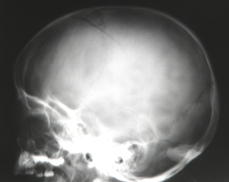

O que pode ser bem visualizado no Rx P?

Região frontal e Parietal.

Hipófise, Sutura Occipital, Sulco da Artéria Meníngea Média.

Como avaliamos se uma Rx P foi bem feita?

Os ângulos mandibulares devem estar bem sobrepostos, alinhados.